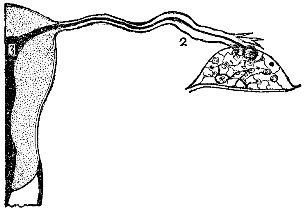

Fig. 2 gives a very good idea of the shape and general structure of this bony framework; while a careful study of Fig. 3 will enable one to form a very correct idea of the relative size and position of the various parts contained in this framework.

By referring again to Fig. 4 it will be seen that the cavity of the body has three openings, one on either side at the top going to the Fallopian tubes, and an opening at the bottom passing into the cavity of the neck. A constriction exists between these two cavities; but after childbirth this is largely done away with, and there is not that marked difference which existed formerly.

|  | |

| Fig. 4. This illustration shows the cavities in a uterus which has been pregnant. 1, the vagina; 2, cavity of the neck of the uterus; 3, cavity of the body, above which is the fundus of the uterus; 4, Fallopian tubes, extending to the ovaries. | Fig. 5. The female generative organs. 1, the vagina; 2, uterus; 3, broad ligament of left side; 4, a smaller ligament; 5, Fallopian tube; 6, ovary; 7, fringed end of Fallopian tube. |

Fallopian Tube.—Figs. 4 and 5 show that there is given off from each side of the upper part of the uterus a tube. This is called the Fallopian tube.

Each tube is about four inches long. Near the uterus its cavity will just admit an ordinary bristle; but near its free end, at the ovary, it is as large as a goose-quill.

It is a peculiar tube in that it terminates in a number of fringe-like processes, one of which is always attached to the ovary itself.

Object of This Tube.—The Fallopian tube conveys the sperm of the male from the uterus to the ovary, and also takes the germ-cell (or ovule, or egg) from the ovary to the uterus.

When a ripe egg is about to be discharged from the ovary, one of these fringe-like processes of the Fallopian tube grasps it and receives it into the mouth of the tube, whence it is conveyed directly into the uterine canal.

| Fig. 8. This figure illustrates the course followed by an ovum. The ripened egg leaves the ovary (1), passes down the Fallopian tube (2), and thence into the uterine cavity (3). | Fig. 9. An exceedingly minute piece of an ovary, highly magnified. It shows eight ova or eggs. |